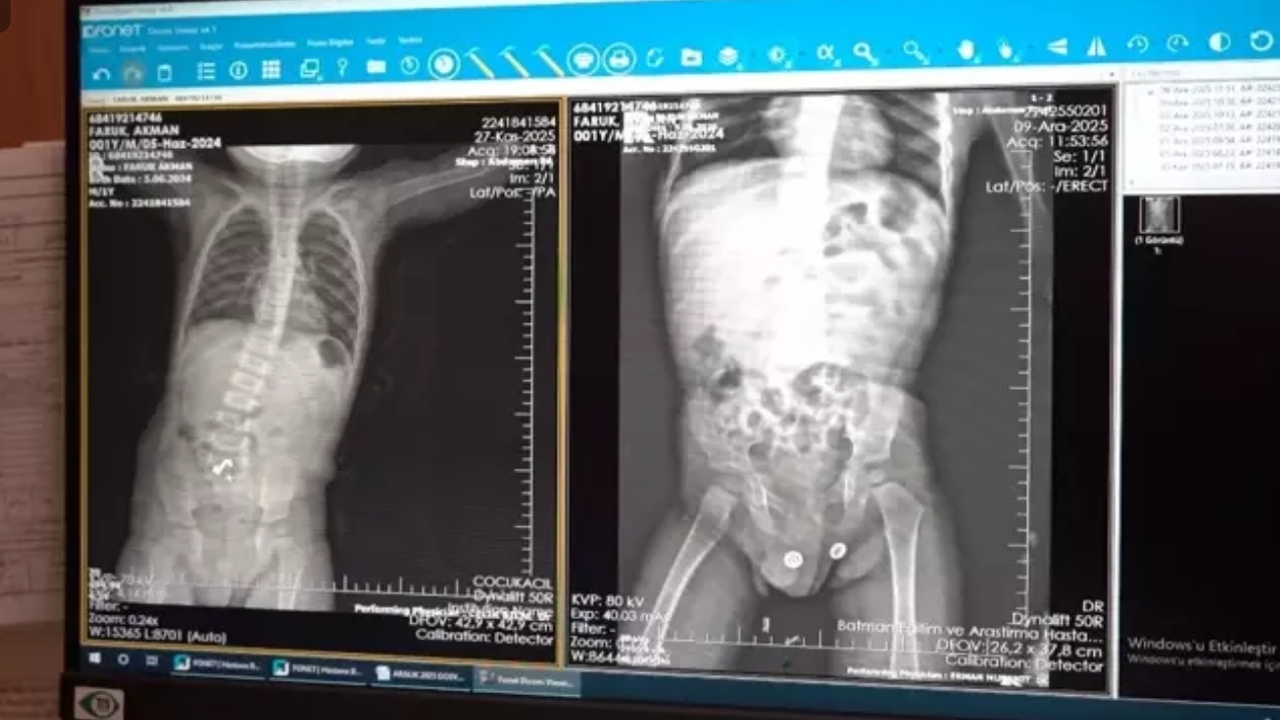

Kusma ve şiddetli karın ağrısı şikâyetleriyle acil servise getirilen küçük Faruk, Çocuk Cerrahisi Kliniği’nde yakın takibe alındı.

Yapılan incelemelerde, mıknatısların sindirim sisteminde ilerlemek yerine bağırsak duvarlarını birbirine hapsettiği saptandı. Mıknatısların yarattığı çekim gücünün organlarda doku kaybına yol açtığı anlaşılınca, Op. Dr. Mücahit Erman liderliğindeki ekip acil müdahale kararı aldı.

Laparoskopi (kapalı yöntem) desteğiyle gerçekleştirilen ameliyatta, mıknatısların bağırsaklarda yarattığı yıkım gözler önüne serildi.

Birbirine kenetlenen mıknatıslar nedeniyle bağırsakların üç ayrı yerden delindiği görüldü.

Uzman ekip, yaklaşık 5 santimetrelik hasarlı bağırsak bölümünü mıknatıslarla birlikte titiz bir çalışmayla tahliye etti.